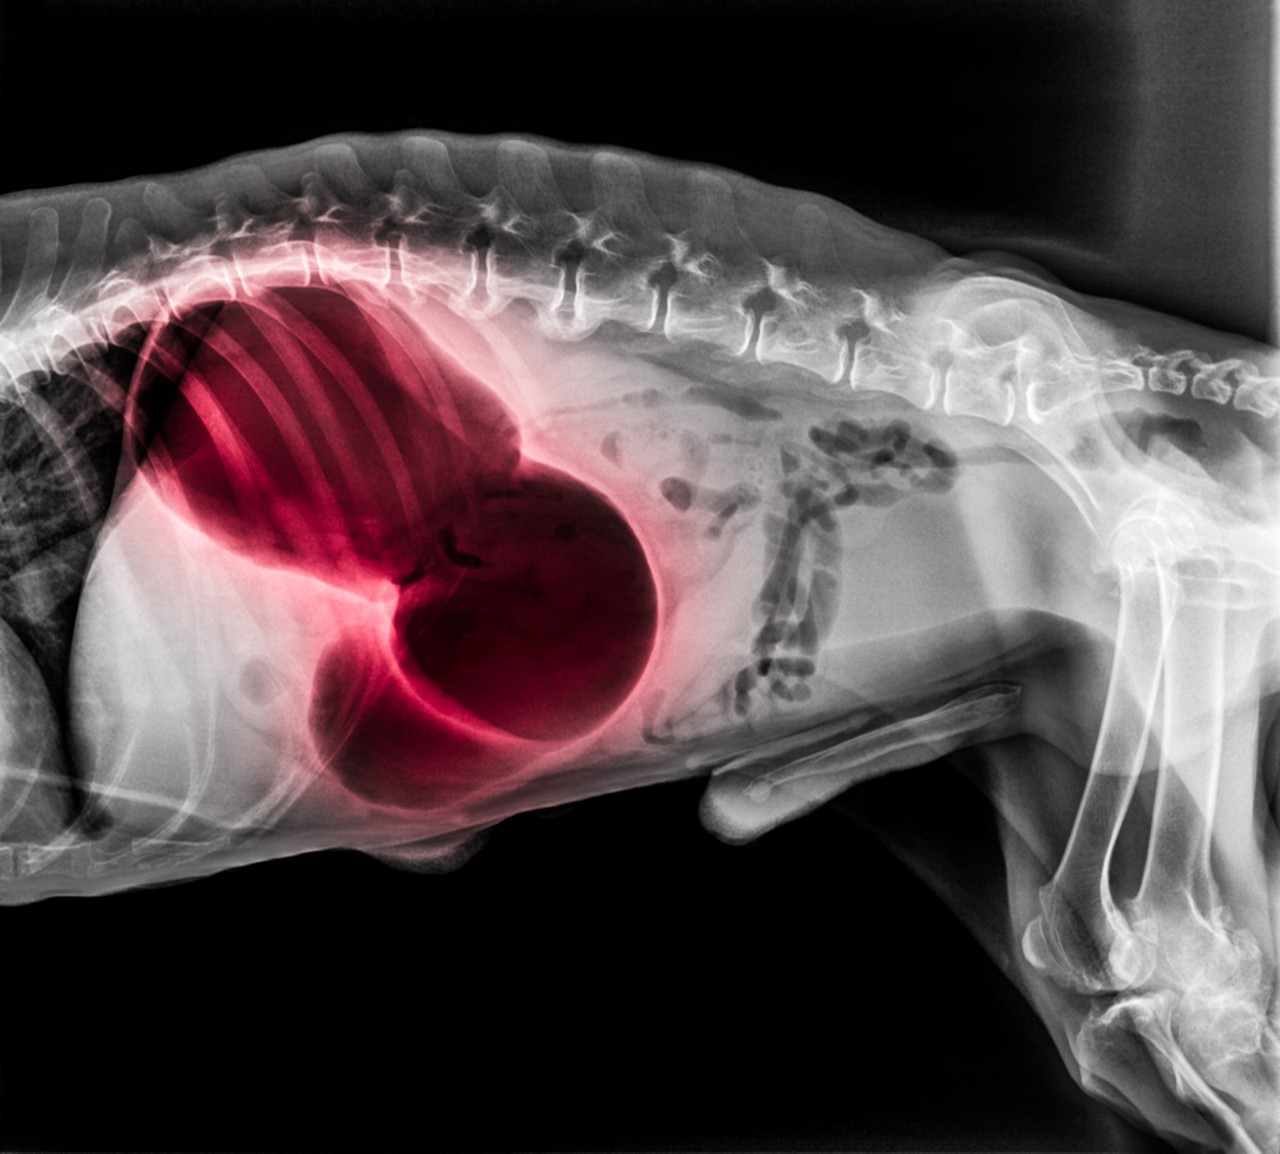

Dog with bloat x ray

Bloat is also called gastric dilatation-volvulus and occurs when the digestive system fills with gas and twists. No-one knows if the gas causes the twists, or the gut twists and then fills with gas. Either way it is an extremely painful condition which can cut off the blood supply to the gut causing damage, stop gas and food passing through the gut, cause the spleen to twist and lose blood supply, and can block vital veins taking blood back to the heart. The gas filled gut also puts pressure on the diaphragm, making breathing difficult.

The vet will take a history, x-ray and probably do blood tests but the only treatment is surgery. The vet will need to un-twist the gut and staple it to the body wall to prevent it twisting again. Sadly, up to a third of all dogs with Bloat die, and the longer they are left bloated the worse their chances are.